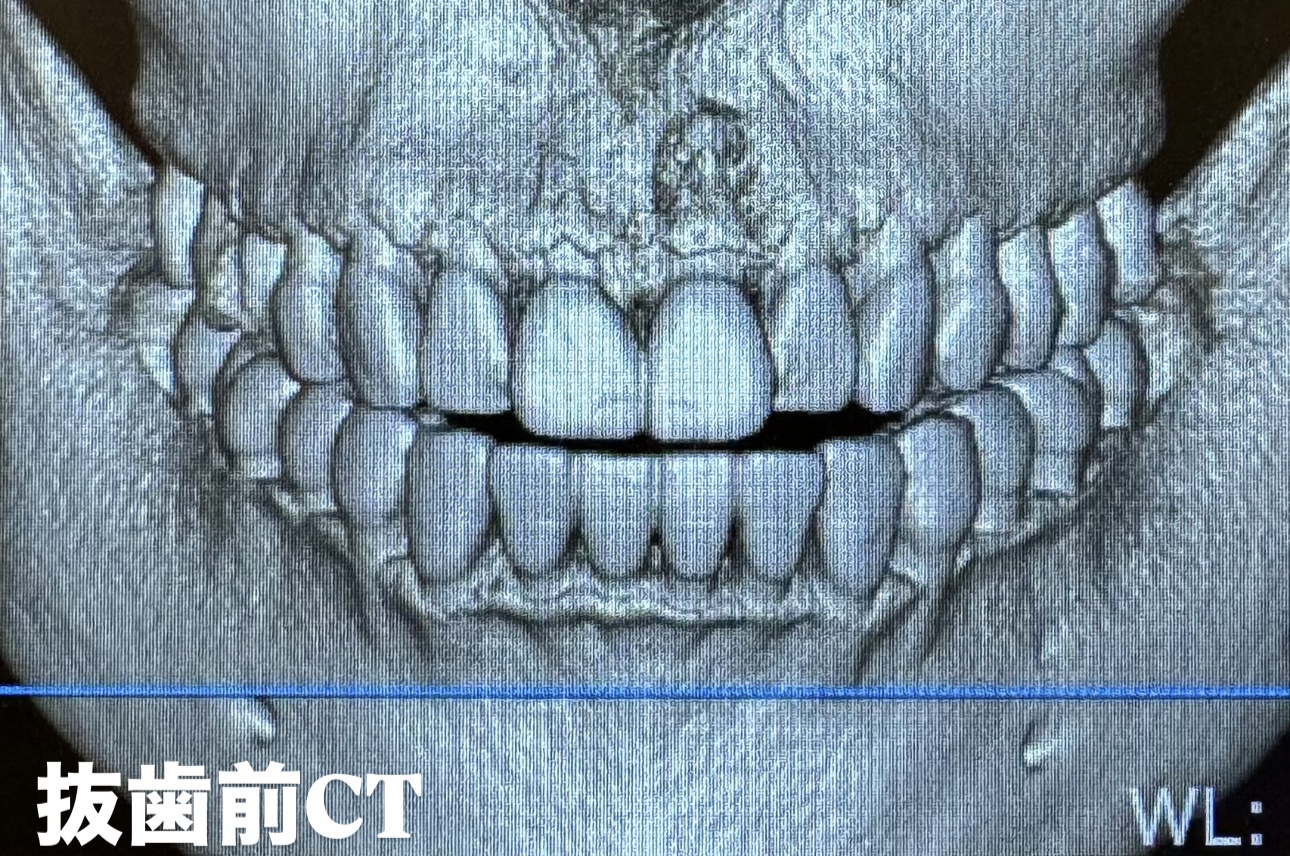

• 前歯のインプラント抜歯即時埋入

前歯のインプラント抜歯即時埋入

• インプラント抜歯即時埋入

インプラント抜歯即時埋入